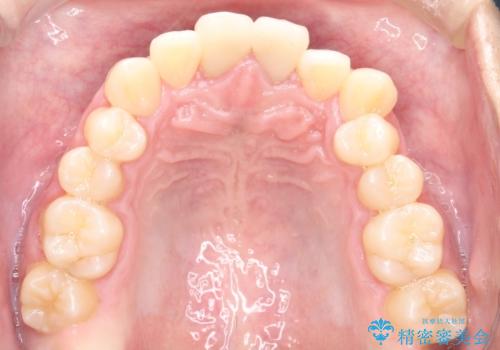

- 前歯のガタガタを主訴に来院されました。

上下の前歯のガタガタと左上の歯が反対にかんでいる状態でした。

上下の歯と歯の間をわずかに削り並べる計画としました。

目立たずに歯並びがよくなり、前歯に装着されたセラミックも壊さずに矯正治療が終了し満足していただけました。